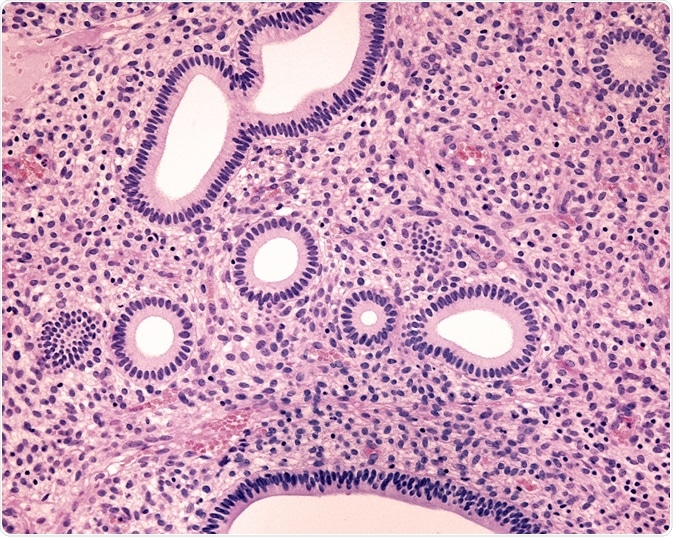

Credit: Jose Luis Calvo/ Shutterstock.com